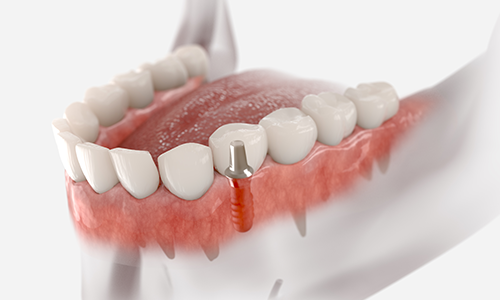

뼈 이식이나 발치 즉시 식립 등 까다로운 조건에서도 정밀 진단과

체계적인 시술 시스템으로 환자 맞춤형 치료를 제공합니다.

오스템 임플란트

오스템 임플란트는 세계적으로 검증된 안정성과 내구성을

자랑하는 임플란트입니다.

정밀한 설계와 품질 관리로 장기적인 안정성을 보장하며,

환자 개개인의 구강 상태에

맞춘 맞춤형 시술이 가능합니다.